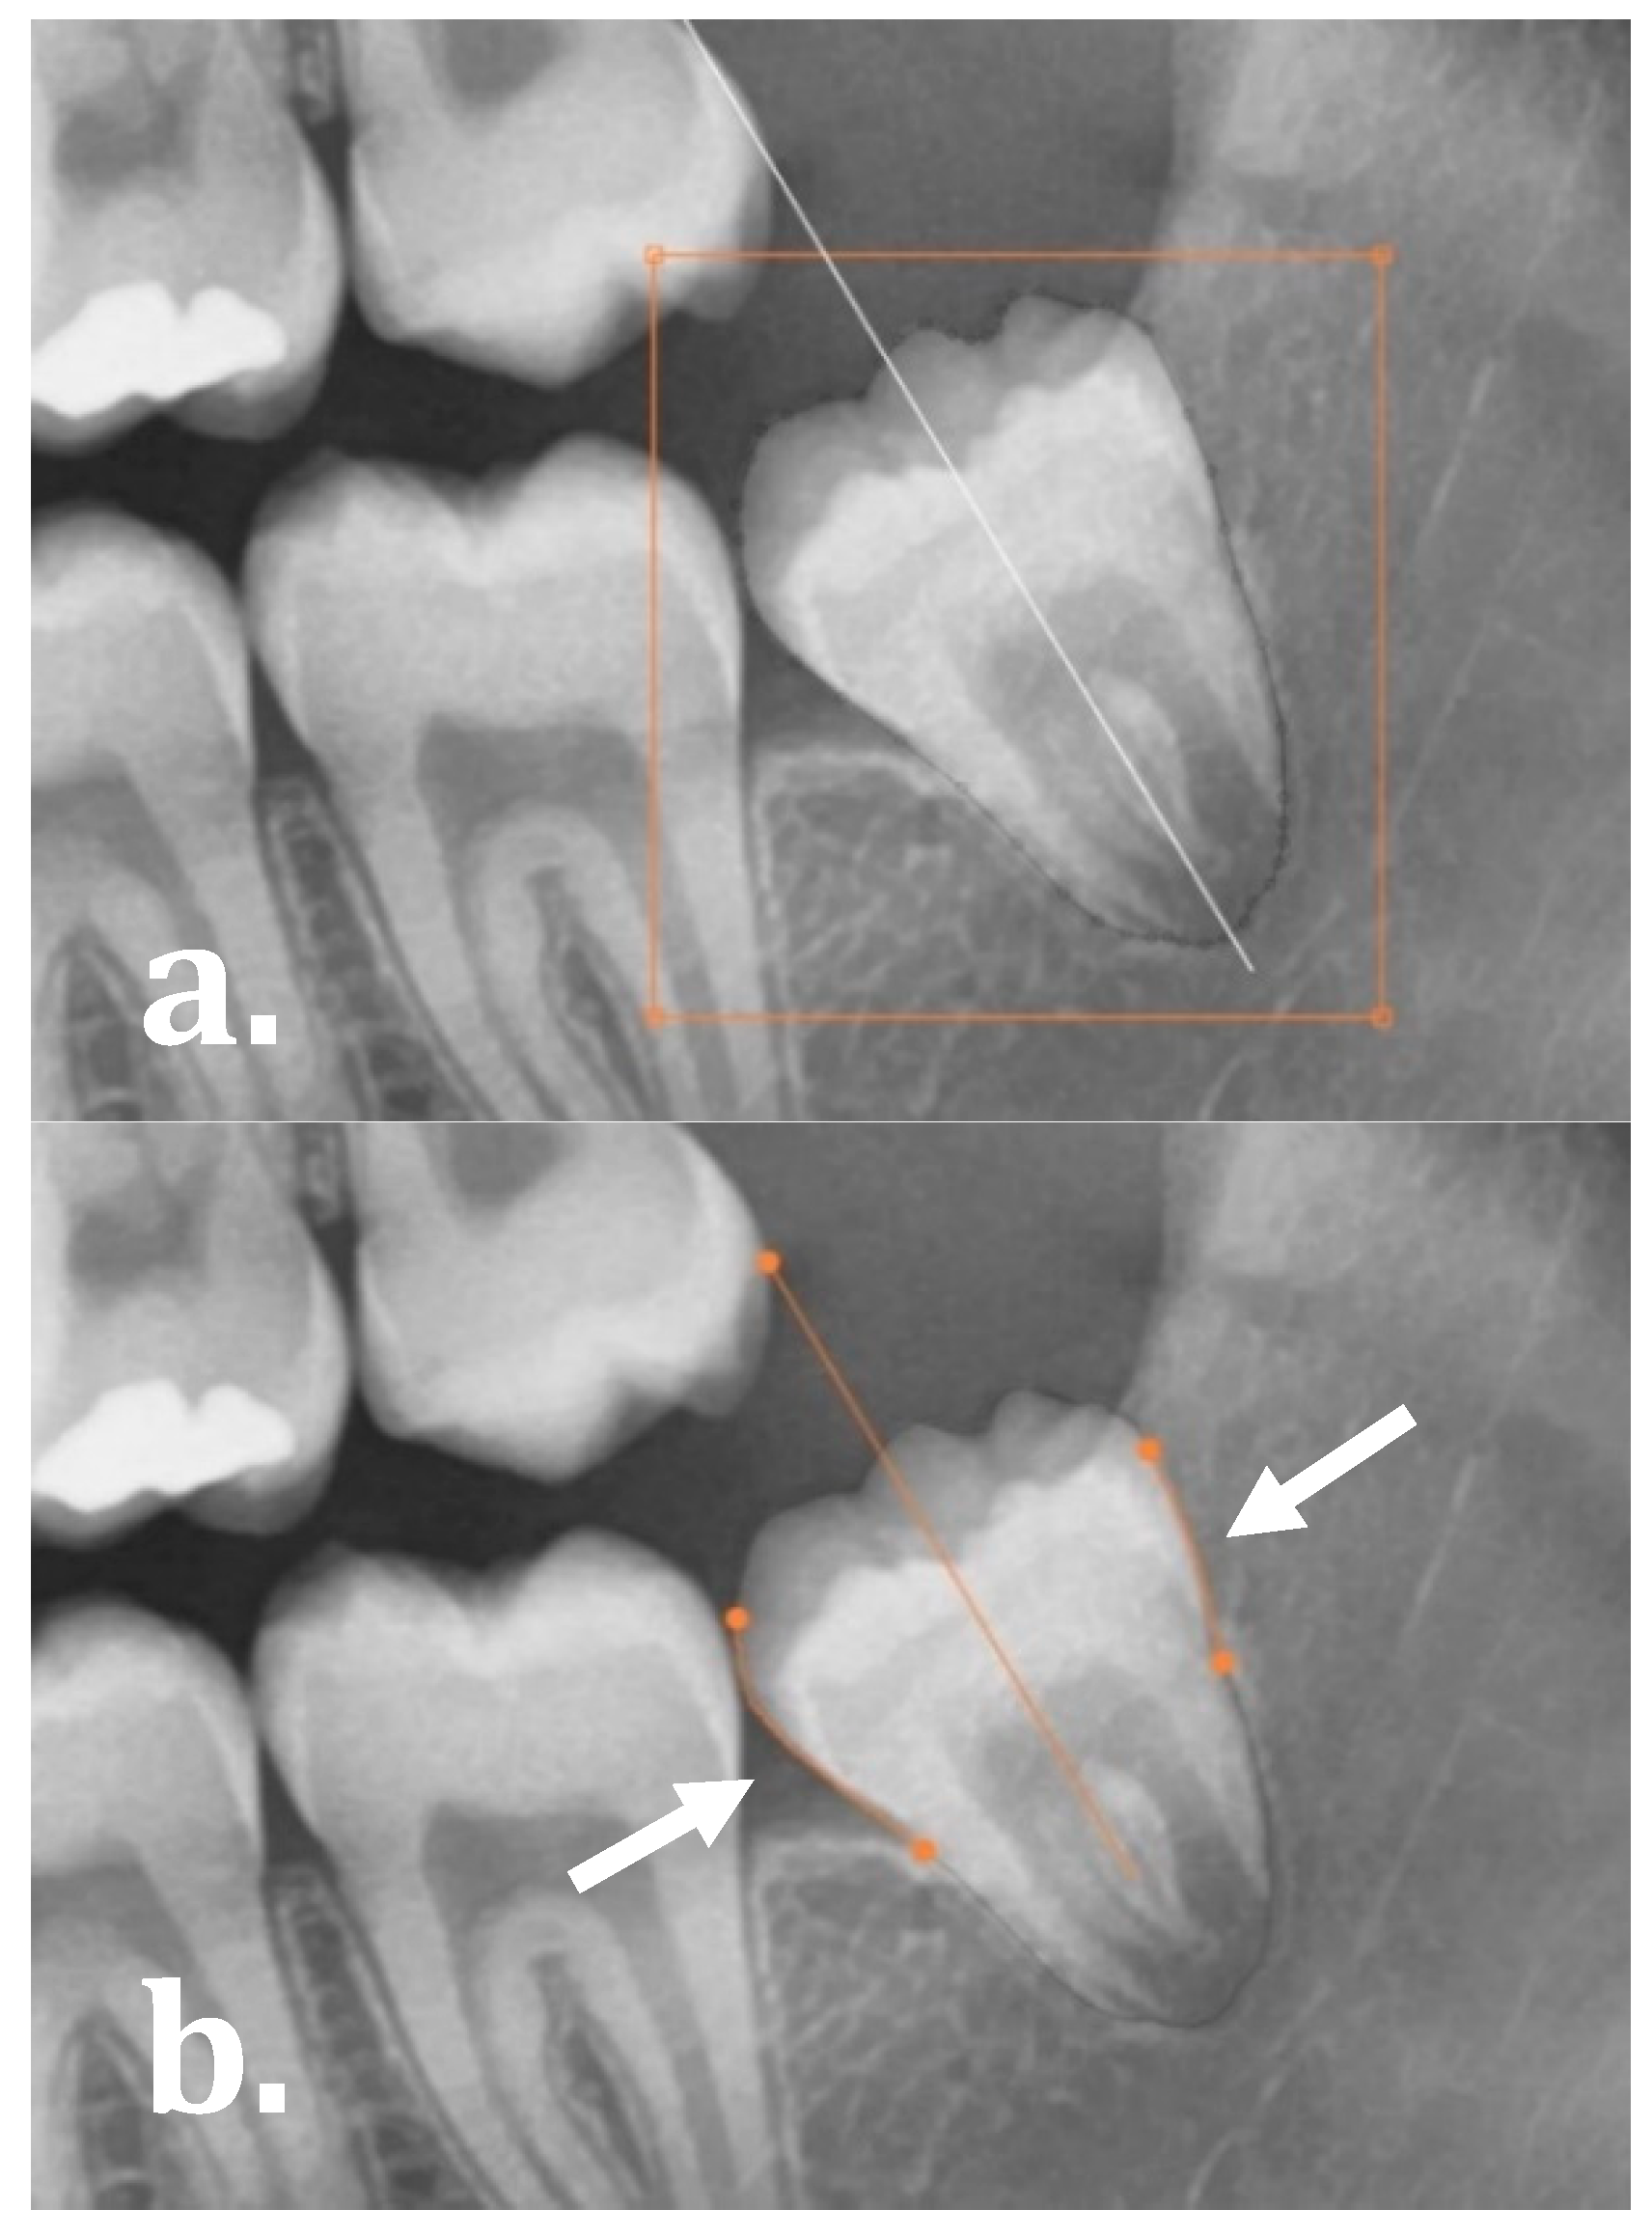

The software allowed for the user to evaluate and manually refine the final molar angulations by either: (1) editing the segmentation map as demonstrated in Figure 3a (drag, cut or re-create segmentation contours), and (2) manually dragging the start and end points of the regression lines on the mesial and distal side of the molars as illustrated in Figure 3b.

Figure 3. Manual adaptations to the network: (a) editing the segmentation map and (b) manipulating the orientation line by manually dragging the mesial and distal regression lines.